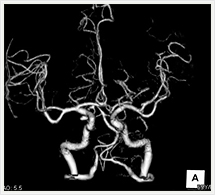

画像紹介

CTでは輪切り像の他にも立体的な画像(3D画像)を作成することもできます。そのためにはより細かくキレイな画像を撮影しなければなりません。当院では64列CTを導入しており、キレイな画像をより細かく撮影することができます。その画像を元に3D画像を作成することによって、より正確な手術のシミュレーションが可能になります。実際に手術をしたときの様子が、手術をする前に画像として見らます。外科系の手術には欠かせない技術となっておりますが、内科系でも血管内手術にも多く利用されております。

当診療放射線技術科では毎日各診療科に対して、その手術に最適な3D画像を提供しております。

以下にその3D画像を一部分紹介します。

頭部